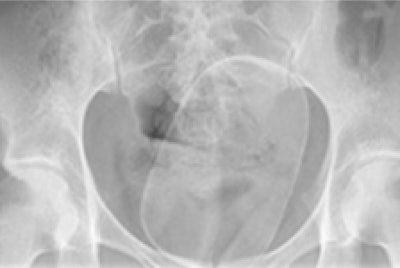

In another case, a 24-year-old woman was found to have a foreign body lodged within her vaginal cavity. On x-ray, a solitary well-defined radiopaque density was lying within the pelvis, outside of the bowel lumen. The patient required examination under anesthetic, episiotomy, suprapubic pressure, and manual delivery of a plastic cylindrical mass weighing 288 g.

X-ray of 24-year-old woman shows a solitary well-defined radiopaque density lying within the pelvis, outside of the bowel lumen.The authors have also encountered cases of colonic packing. They have seen smooth, well-defined radiopaque densities -- sometimes variable in size and shape -- scattered throughout the bowel lumen. The characteristic 'double condom' sign may be visible, and the complications can include bowel obstruction or perforation.